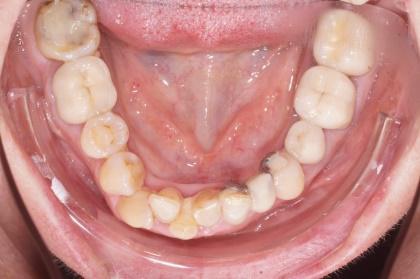

Un travail collaboratif

L’orthodontiste doit travailler en collaboration avec une équipe d’autres spécialistes pour définir un calendrier thérapeutique et donner au patient adulte le meilleur résultat.

- Intégrer la réalisation des prothèses et des implants

- Diagnostiquer les différents stades de la maladie parodontale (maladie de l’os et des gencives) et des facteurs de risque associés.